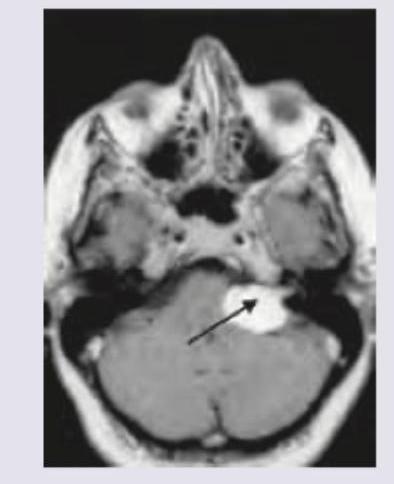

Explanation: ***Acoustic neuroma*** - Progressive **unilateral hearing loss** and **tinnitus** are classic symptoms due to compression of the **vestibulocochular nerve (CN VIII)**. - **Numbness around the posterior aspect of concha** indicates involvement of **Arnold's nerve (auricular branch of vagus nerve, CN X)**, which supplies sensory innervation to this area. This finding suggests tumor extension and is consistent with a larger acoustic neuroma. - The presented MRI shows a mass in the **cerebellopontine angle**, typical for an acoustic neuroma (a vestibular schwannoma arising from CN VIII). *Astrocytoma* - Astrocytomas are primary brain tumors that typically arise within the **brain parenchyma** and rarely present with isolated otologic symptoms. - They would not typically cause **concha numbness** through cranial nerve compression in this specific pattern. *Meningioma* - Meningiomas are typically **dural-based tumors** and can occur in the cerebellopontine angle, but they are less common than acoustic neuromas in this location. - While CPA meningiomas can cause cranial nerve symptoms, the specific combination of **CN VIII symptoms with Arnold's nerve involvement** is more characteristic of acoustic neuroma. *Straight sinus thrombosis* - Straight sinus thrombosis causes symptoms related to **increased intracranial pressure**, such as severe headache, seizures, and focal neurological deficits. - It would not cause **unilateral hearing loss**, **tinnitus**, or **localized concha numbness** through cranial nerve compression.

Explanation: ***V*** - The image shows a large **right cerebellopontine angle (CPA) mass**, consistent with an **acoustic neuroma** (vestibular schwannoma), which commonly arises from CN VIII in the internal auditory canal and extends into the CPA. - The **trigeminal nerve (CN V)** is the most common extracanalicular cranial nerve to be compressed and involved by larger CPA tumors due to its proximity and superior-anterior position relative to CN VIII. *VI* - The abducens nerve (CN VI) controls the lateral rectus muscle of the eye, and its involvement typically causes **diplopia** and **lateral gaze palsy**. While possible with very large and medially extending CPA tumors, it is less common than CN V involvement. - CN VI is located more medially and anteriorly within the brainstem and generally requires significant mass effect rather than direct compression from a typical CPA tumor. *VII* - The facial nerve (CN VII) travels with the vestibulocochlear nerve (CN VIII) through the **internal auditory canal**, and is frequently involved by acoustic neuromas within the canal, leading to **facial weakness or paralysis**. - However, the question specifically asks for the most common **extracanalicular** nerve involvement. While CN VII is intimately associated, its most common site of involvement is within the canal, or early in the CPA, and V is often implicated with larger CPA masses. *VIII* - The vestibulocochlear nerve (CN VIII) is the nerve from which **acoustic neuromas (vestibular schwannomas)** originate, causing the presenting symptoms of **unilateral SNHL and tinnitus**. Therefore, it is the primary affected nerve, not an extracanalicular one involved due to compression. - The question asks for the most common **extracanalicular nerve to be involved**, implying a nerve *other than* the one the tumor originates from or primarily affects locally within the canal.

Explanation: ***Acoustic neuroma*** - The combination of **progressive unilateral hearing loss**, **balance difficulties**, and **headaches**, along with an **enhancing mass in the cerebellopontine angle** on MRI, is highly characteristic of an acoustic neuroma (vestibular schwannoma). - These are benign tumors that arise from the **vestibulocochlear nerve (cranial nerve VIII)**, causing compression of adjacent structures. *Vestibular neuritis* - This condition presents with **sudden onset, severe vertigo** often triggered by head movement, but it is typically **acute and self-limiting**, without a progressive course or an intracranial mass. - **Hearing is usually spared** in vestibular neuritis, which is inconsistent with the patient's progressive hearing loss. *Otosclerosis* - Otosclerosis is a disease of abnormal bone remodeling in the middle ear, leading to **progressive conductive hearing loss**, often bilateral. - It does **not typically cause balance difficulties** or present as a **cerebellopontine angle mass** on MRI. *Meniere's disease* - Characterized by a triad of **fluctuating hearing loss**, **episodic vertigo**, and **tinnitus**, often with a sensation of aural fullness. - While it causes hearing loss and balance issues, it does **not involve an enhancing mass** in the cerebellopontine angle.